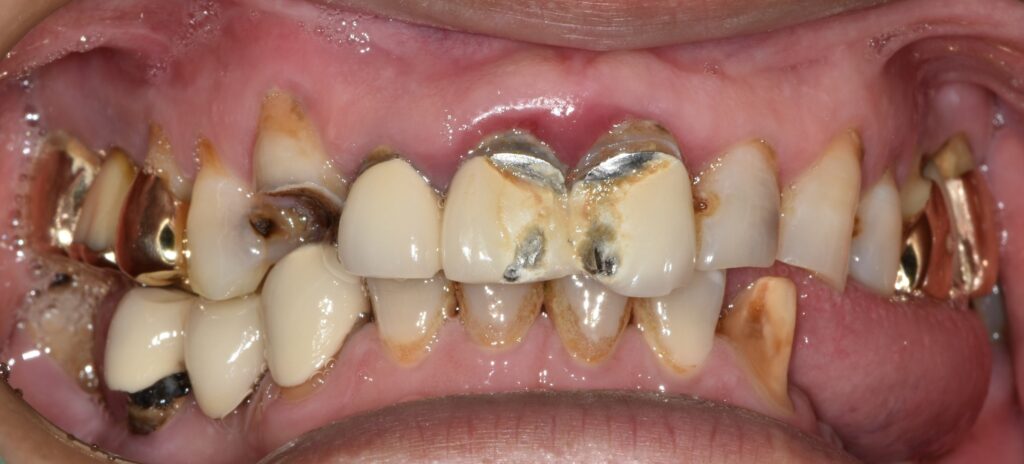

한 40대 남성이 치과에 찾아왔습니다. 치아 전체가 안 좋은데 참고 지내다가 도저히 안되겠기에 큰 맘먹고 치료받으러 오셨다고 하네요.

상태는 위와 같았습니다. 아래 앞니를 제외하고는 전부다 문제가 있는 상황이었습니다.

1. 치아 상실

2. 깊은 충치

3. 심한 잇몸 염증

4. 치아 부러짐 등

발생할 수 있는 모든 문제점들이 다 발생해 있었습니다.